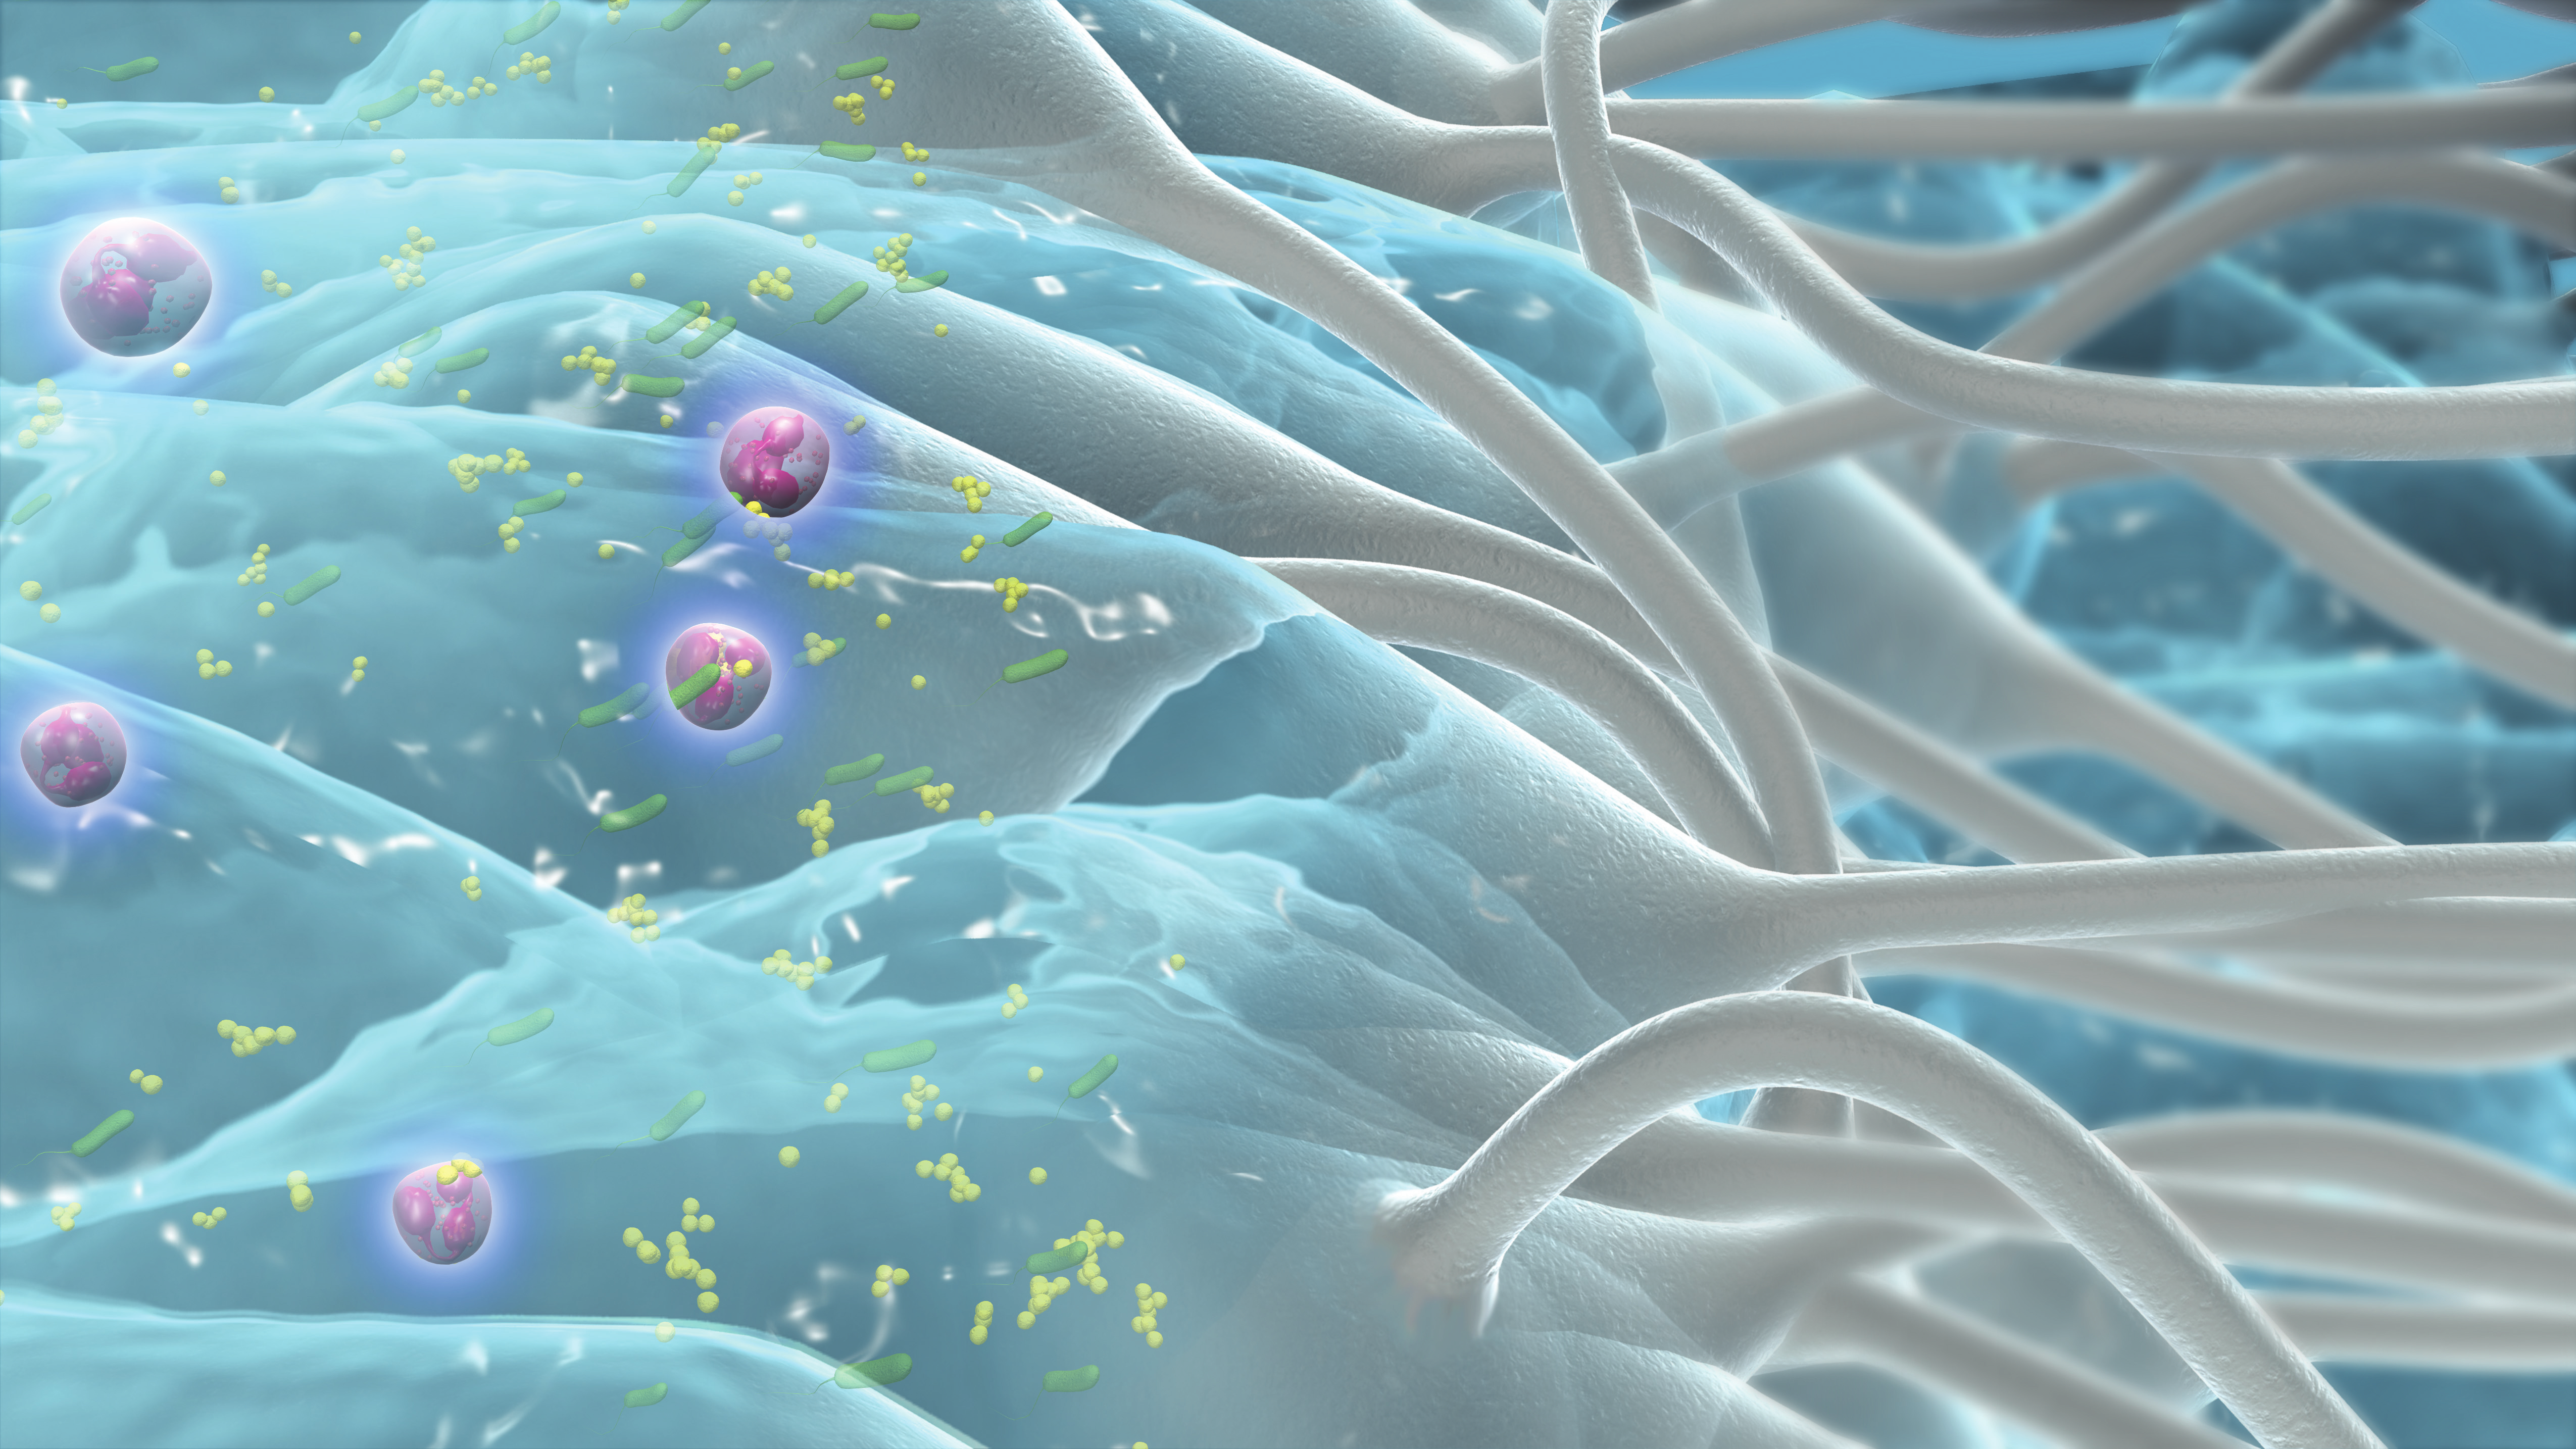

Retiene el exudado de la herida y las bacterias contenidas en él*1-3

Ayuda a proteger la piel perilesional y evita la maceración4, 5

Puede ayudar a minimizar la infección cruzada durante la retirada6, 7

Prueba de secuestro

2. Walker M, Hobot JA, Newman GR, Bowler PG. Scanning electron microscopic examination of bacterial immobilisation in a carboxymethylcellulose (Aquacel) and alginate dressings. Biomaterials. 2003;24(5):883.-890.

3. Newman GR, Walker M, Hobot J, Bowler P. Visualisation of bacterial sequestration and bactericidal activity within hydrating Hydrofiber® wound dressings. Biomaterials. 2006;27:1129-1139.